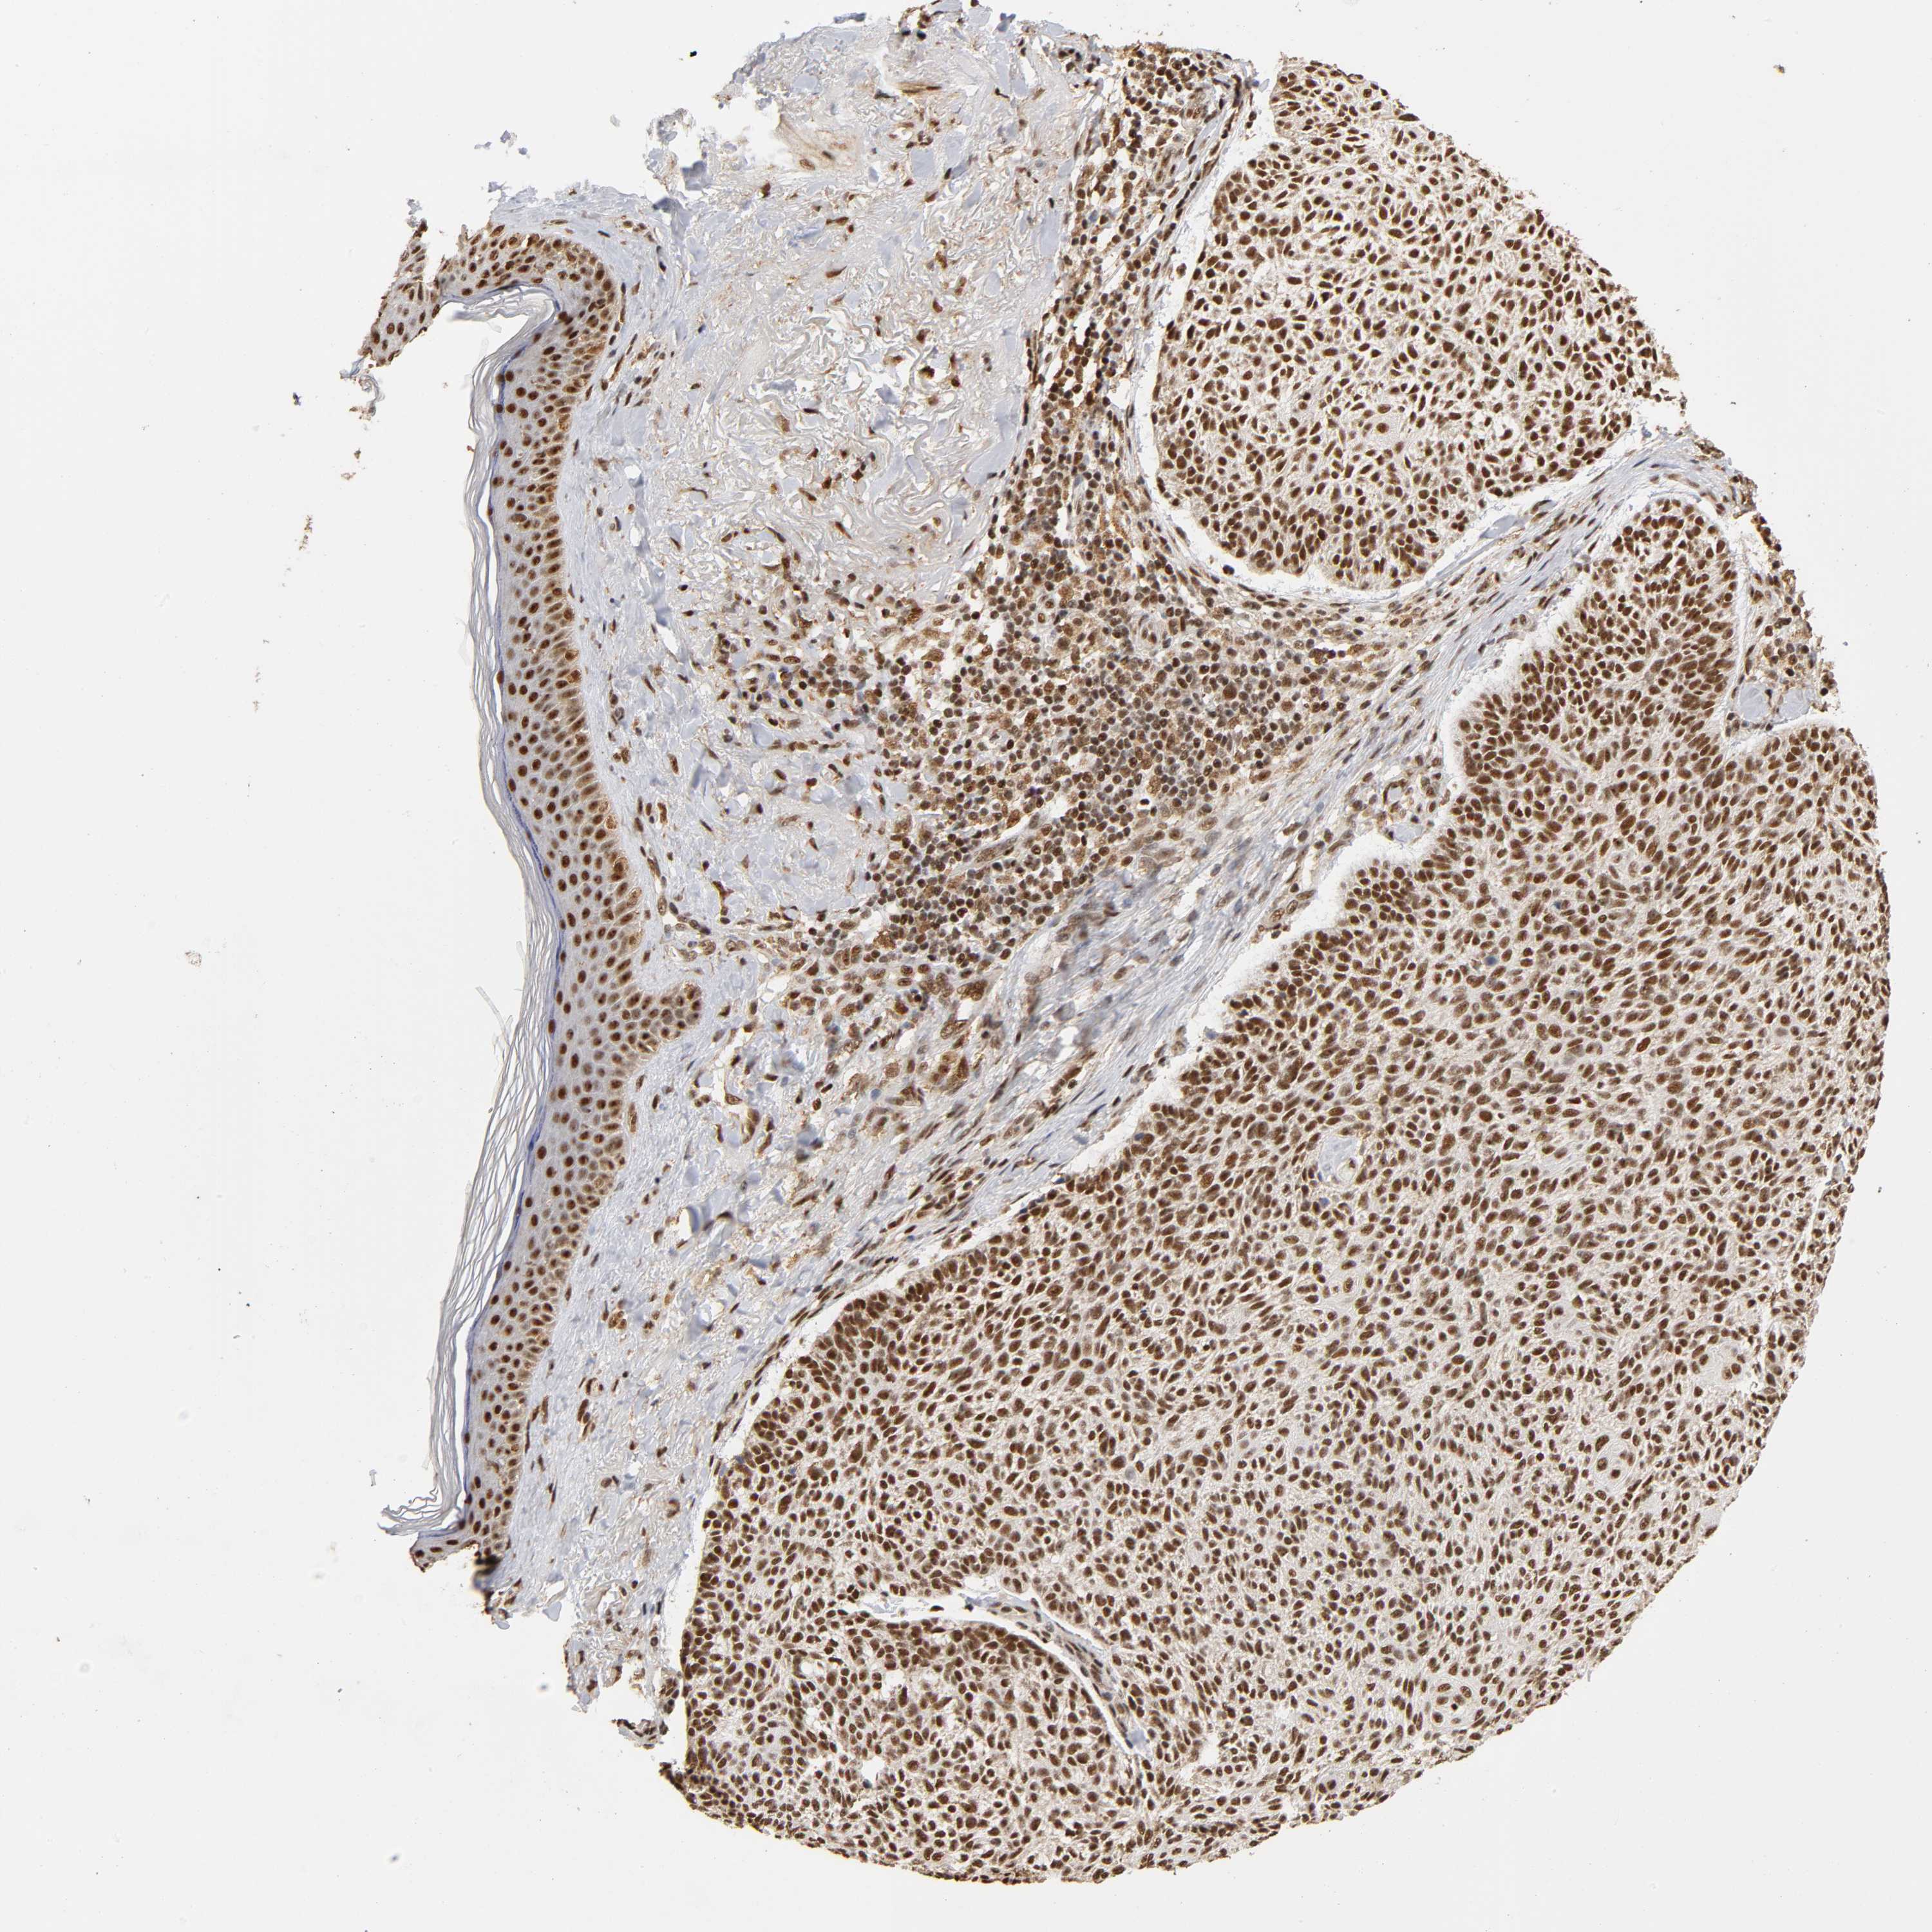

SKIN CANCER - Protein expressioni

A mouse-over function shows sample information and annotation data. Click on an image to view it in a full screen mode. Samples can be filtered based on level of antibody staining by selecting one or several of the following categories: high, medium, low and not detected. The assay and annotation is described here.

Antibody stainingi

Antibody staining in the annotated cell types in the current human tissue is reported as not detected, low, medium, or high, based on conventional immunohistochemistry profiling in selected tissues. This score is based on the combination of the staining intensity and fraction of stained cells.

Each image is clickable and will lead to virtual microscopy that enables deeper exploration of all samples and also displays staining intensity scores, fraction scores and subcellular localization as well as patient and tissue information for each sample.

Antibody HPA003888

Staining

High

Intensity

Strong

Quantity

>75%

Location

Nuclear

Squamous cell carcinoma, NOS